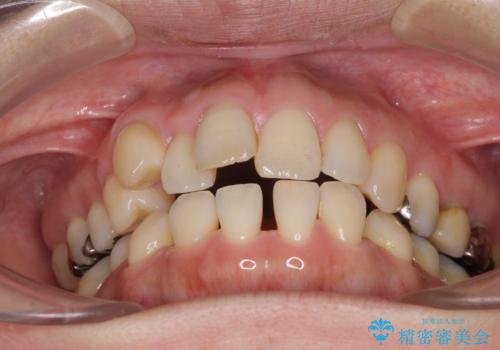

上顎左右第1小臼歯を抜歯したことで、隙間が閉じた下顎歯列の位置まで前歯を引っ込ますことができたため、口の閉じにくさを解消することができました。